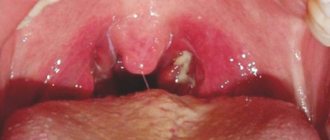

Babies often open their mouths and show their uvula if they have inflammation in the mouth. Among the most common diseases in childhood, pediatricians identify candidiasis and stomatitis.

When there is a fungal infection of the mucous membrane (candidiasis) of the oral cavity, children stick out their tongues, trying to get rid of the discomfort. A one-month-old baby becomes infected with the disease from its mother during feeding or during childbirth.

• The so-called thrush (an infectious fungal disease that affects the baby’s oral mucosa) is a common problem that parents face. Due to the whitish coating on the cheeks, gums, and especially the tongue, the child can stick it out, chew and suck. In addition to dense deposits, the child may feel pain and discomfort. To identify and treat the disease, you need to consult a pediatrician.

Thrush (candidiasis)Often you can see white on the baby's cheeks and palate.If you see a strange plaque in your baby's mouth, you should contact your pediatrician.Oral swab for fungus (candida).